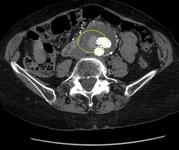

Type II endoleak (encircled) discovered on follow-up CT

University of Michigan, specifically the cases of Dr Upchurch reflecting the Departments of Vascular Surgery and Radiology